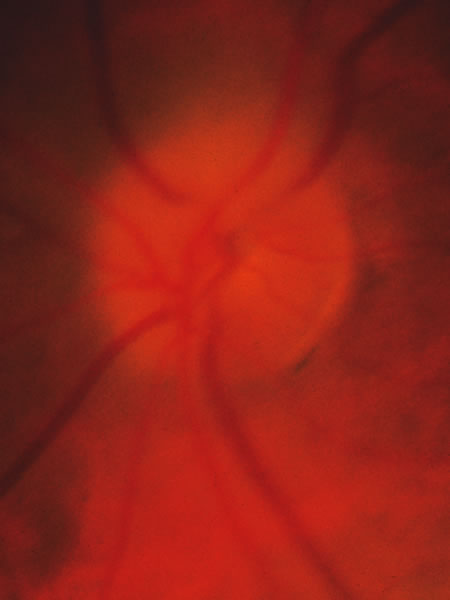

In acute angle-closure glaucoma (Fig. 33), the optic disc may swell,147–149 perhaps as a result of ischemia, but because of corneal edema and preoccupation with the angle status, it is not often seen. Even after an attack lasting several days, there is often no visual loss; the disc may remain normal appearing or may develop some degree of pallor resembling that of nonglaucomatous optic atrophy.150–152 Excavation of the disc does not seem to result from an acute attack but may result from persistent residual pressure elevation after the attack. If excavation is already present at the time that a patient presents with symptomatic angle closure, the cupping is evidence that for some time an asymptomatic, perhaps gradual, rise of intraocular pressure elevation preceded the abrupt onset of symptoms.

Fig. 33. Swollen disc tissue during an acute attack of angle closure glaucoma.